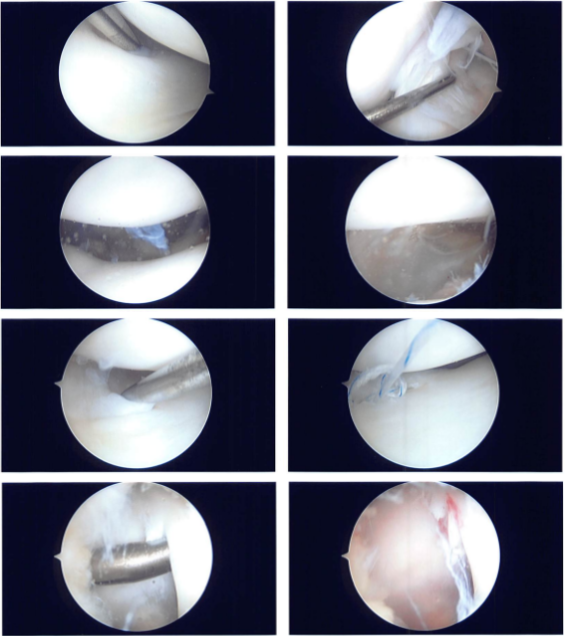

The cartilage was not damaged. The patellofemoral compartment was found to have complete cartilage. It was chosen to repair the medial meniscus tear. The tear was prepped with a rasp and shaver, and a FasT-Fix and arthroscopy were introduced through the lateral portal and the medial portal, respectively.

A horizontal mattress suture was placed and then cut. Fixation was successful. Photographs were taken and preserved. The lateral meniscus posterior horn was also shaved, and photographs were taken and stored.

Chondroplasty picks were used, as well as four microfractures, to allow bone marrow venting. Fat globules, followed by blood, could be observed venting out of the holes to help the meniscus mend faster. The final photographs were shot and preserved. The knee had been completely irrigated and drained.

Intraoperative Images